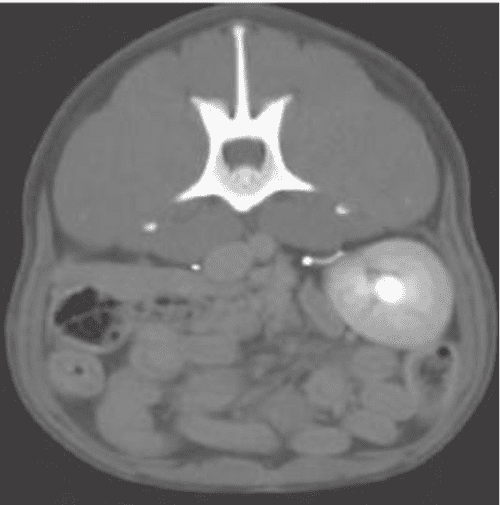

Computed tomography urography and threedimensional reconstructions. A Laser Ablation Ectopic Ureter Dog Using a cystoscope, a laser fiber is used to open up the membrane separating the. Using a cystoscope, a laser fiber is used to open up the membrane separating the ectopic ureter(s) from the urethra, so both ureters then open in the. Retrospective study from 2011 to 2018. This minimally invasive procedure is performed under anesthesia. Laser Ablation Ectopic Ureter Dog.